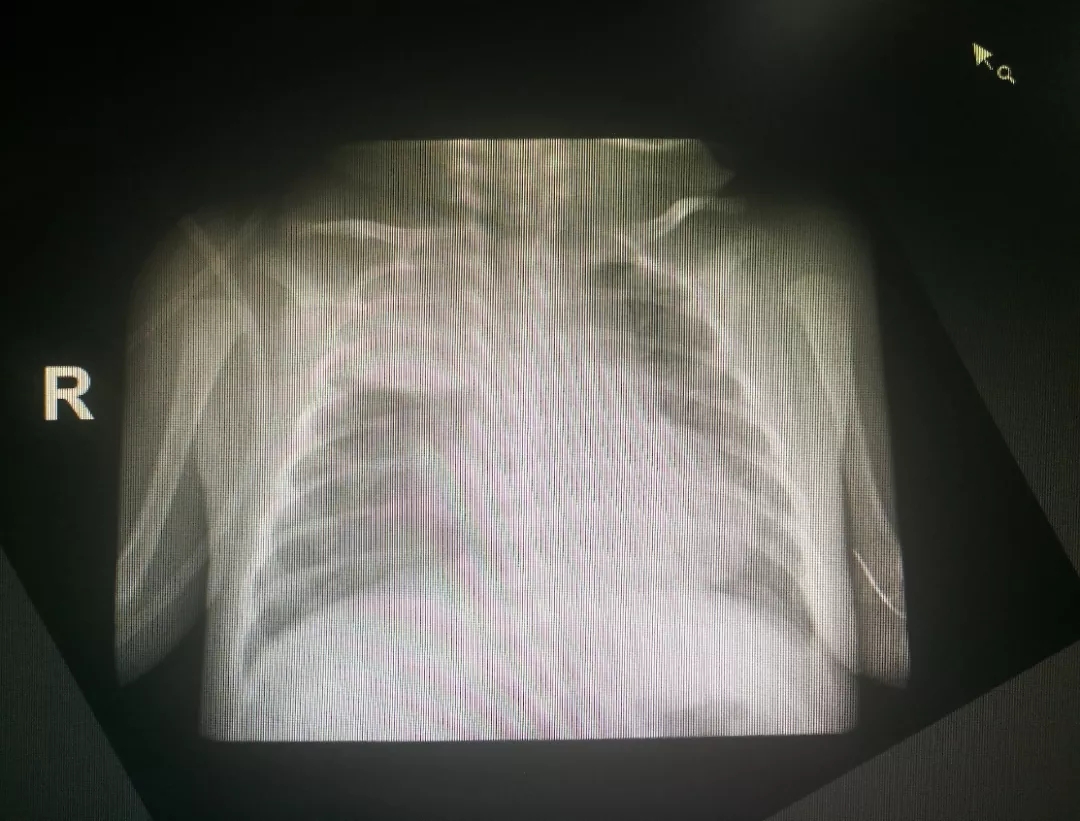

术前胸片